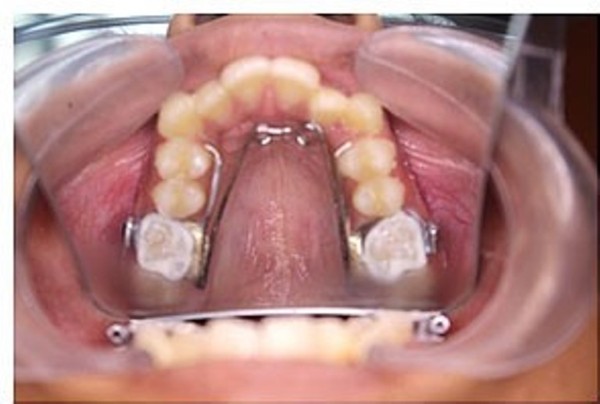

Nong hàm cố định

Đây là kỹ thuật sử dụng khí cụ cố định gắn trực tiếp vào răng để duy trì hoặc mở rộng khung hàm lâu dài. Phương pháp này phù hợp với những bệnh nhân cần mở rộng nhanh, cần độ chính xác cao.

Khí cụ cố định giúp hạn chế việc tháo lắp không đúng quy trình, từ đó nâng cao hiệu quả điều trị. Trong quá trình thực hiện, bác sĩ sẽ kiểm tra định kỳ để điều chỉnh khí cụ phù hợp với mức độ mở rộng mong muốn.

Phương pháp này thích hợp cho cả trẻ em và người trưởng thành, đặc biệt khi những phương pháp khác không đạt đủ hiệu quả hoặc bệnh nhân cần kết quả rõ rệt hơn trong thời gian ngắn.